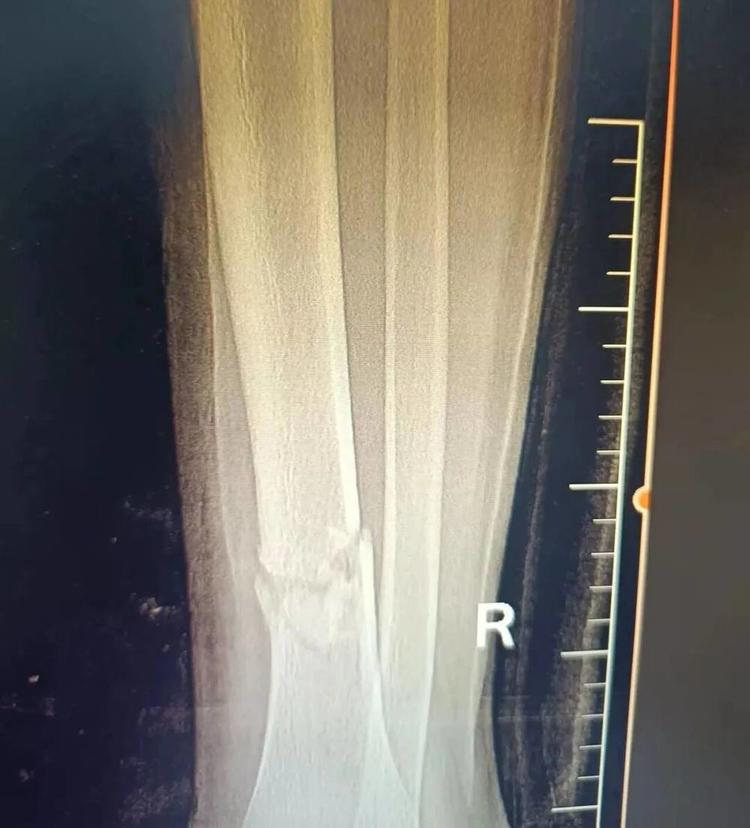

患者王某因意外导致胫骨中下段骨折,家人心急如焚地带他来到益民中西医结合诊所,经仔细检查后,运用陈氏正骨手法为其精准复位,配合特制膏药外敷。在系统调理下,小王的骨骼日渐愈合,恢复情况良好。

▲治疗前后对比